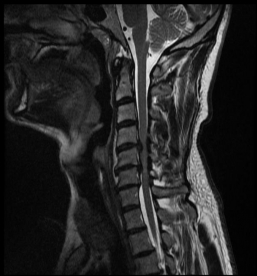

MRI with lateral reconstruction of the cervical spine and a lateral postoperative radiographic check. On the left, an hourglass-shaped constriction of the spinal cord can be seen. The right image shows the condition after surgical decompression and stabilization.